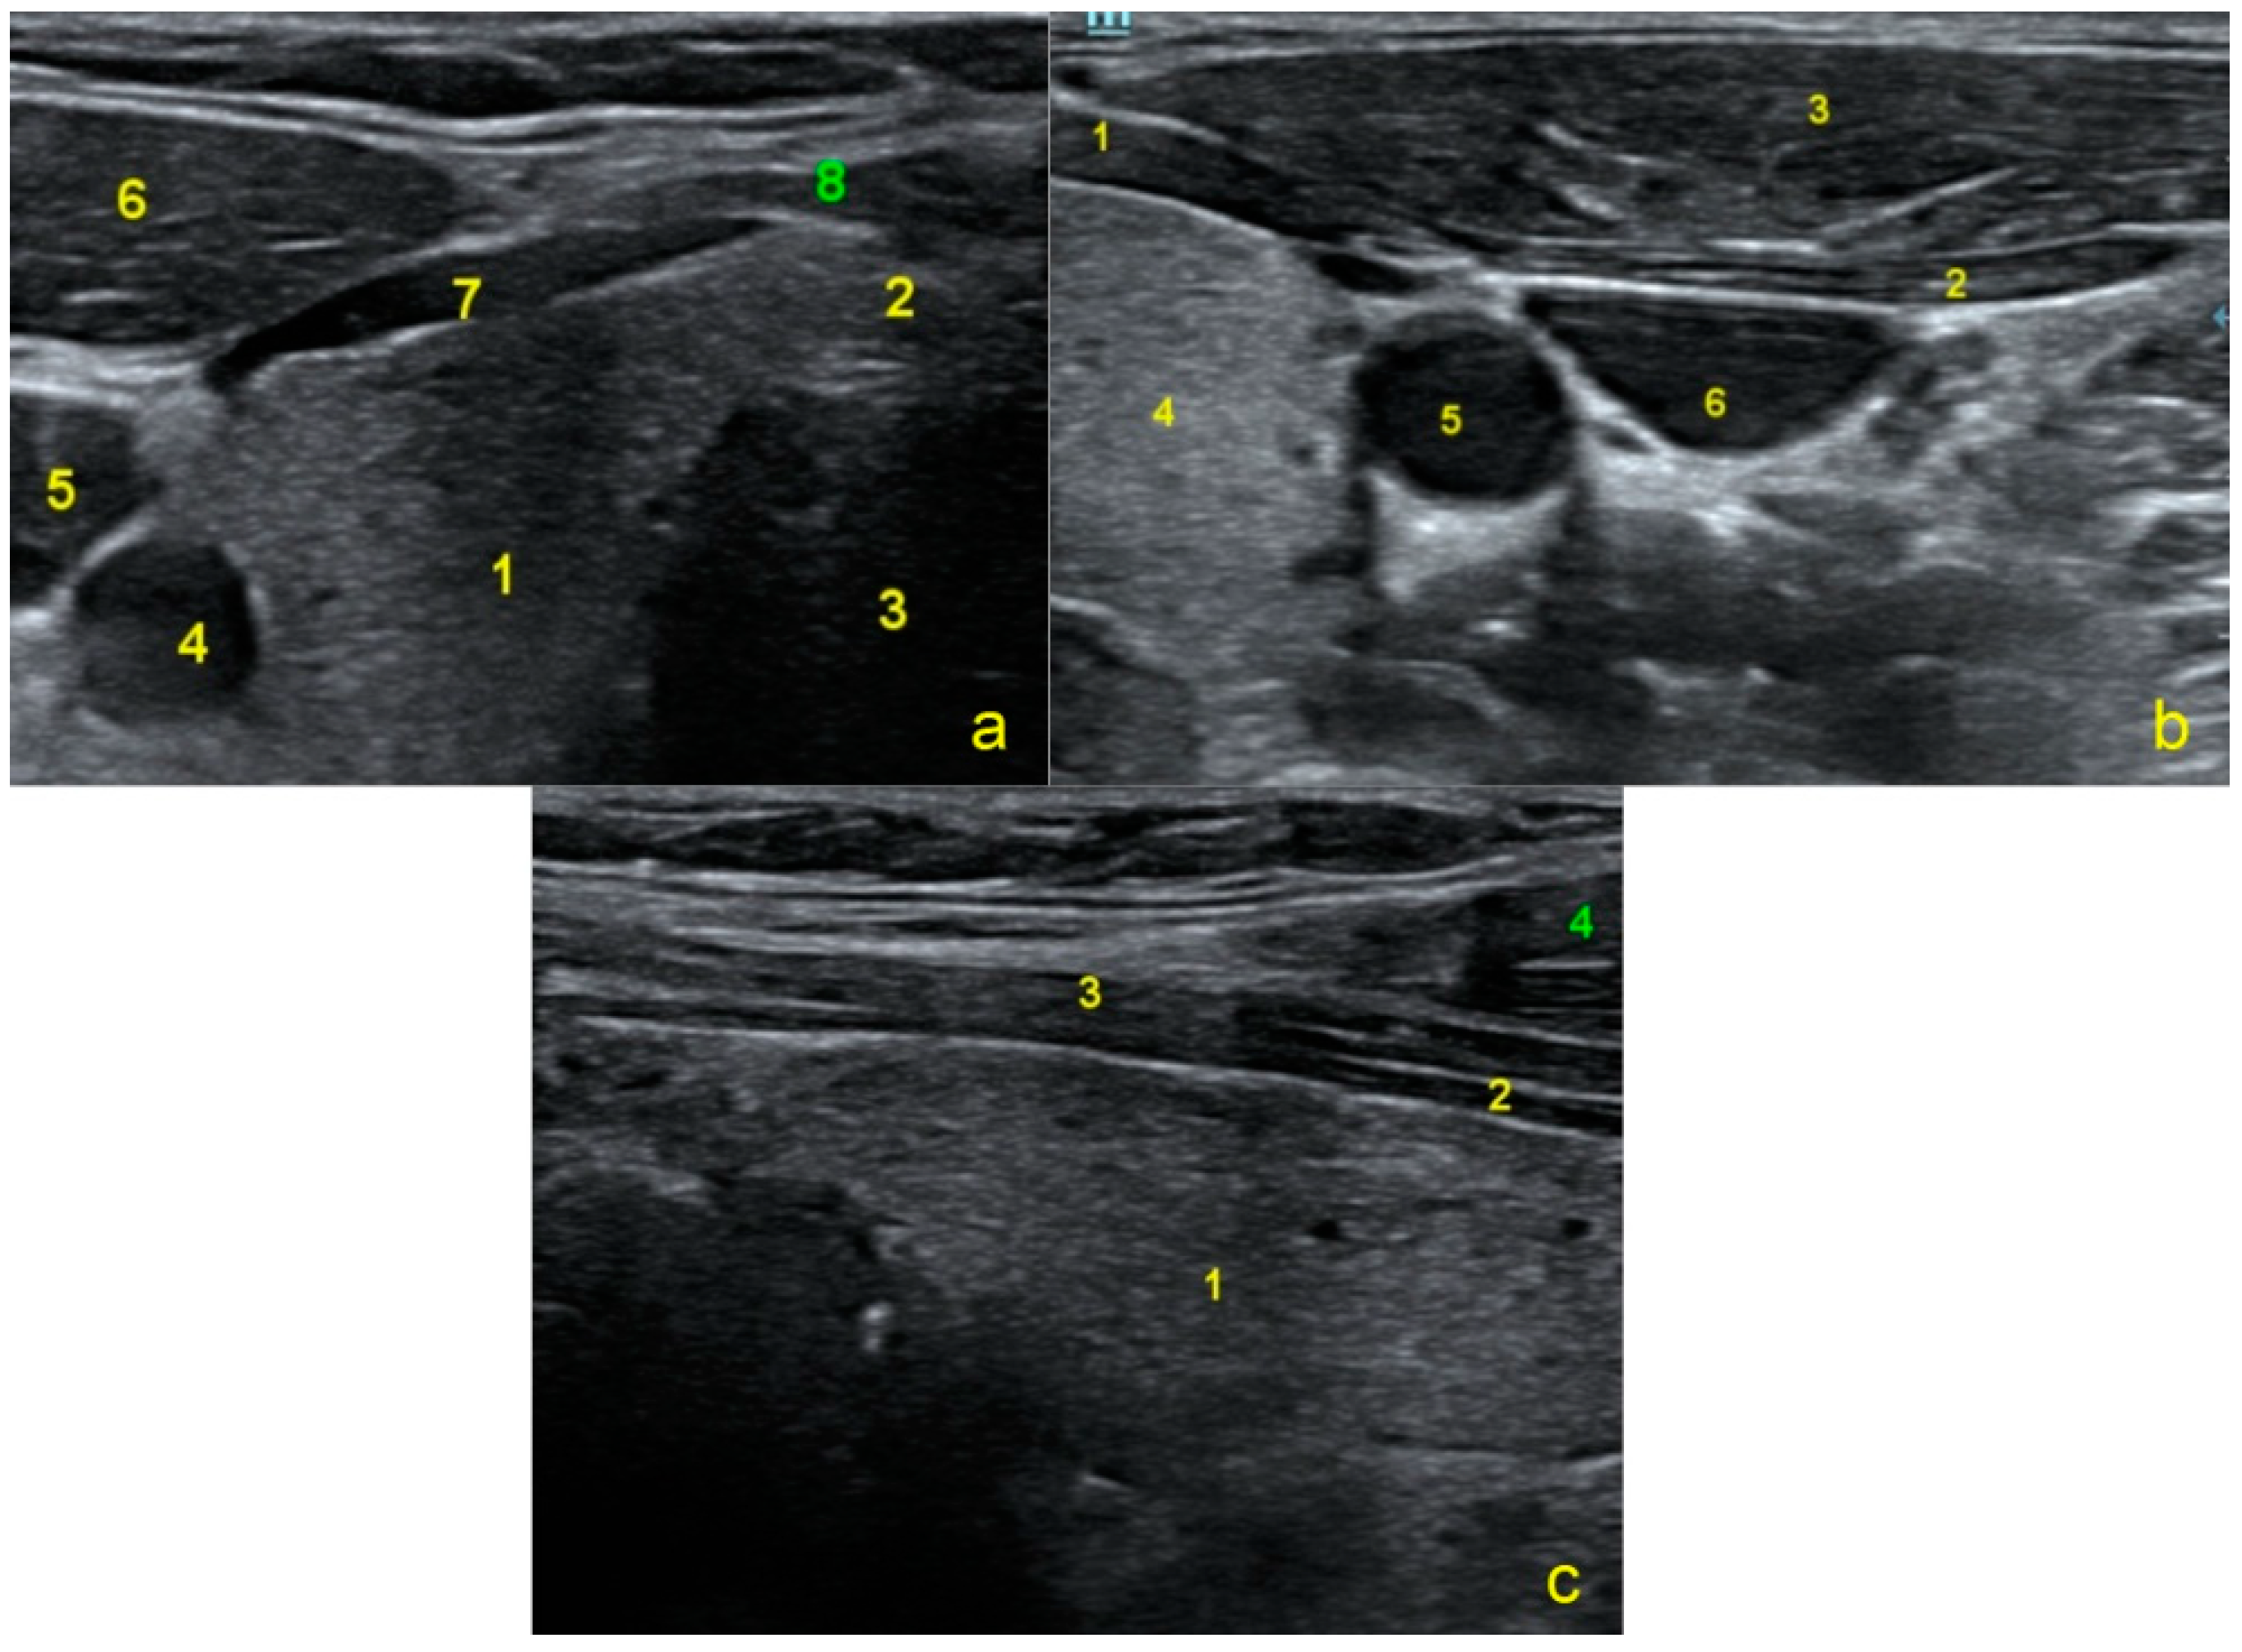

2.2. Surgical Technique (Video 1)

2.2.3. Surgical Technique